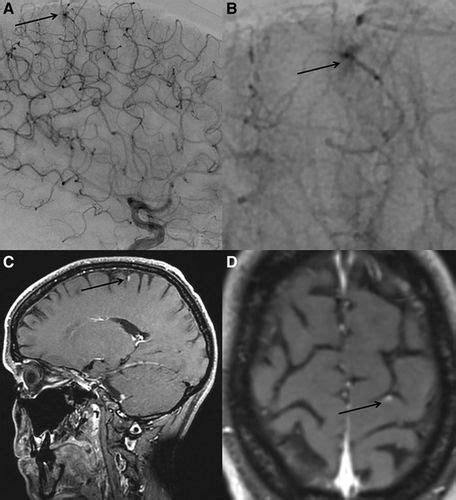

Hht is a genetic condition that causes blood vessels in part of the body to develop abnormally. Hereditary hemorrhagic telangiectasia is a disorder that results in the development of multiple abnormalities in the blood vessels.in the circulatory system, blood carrying oxygen from the lungs is normally pumped by the heart into the arteries at high pressure. People with hht develop small lesions called telangiectases, which can burst and bleed. The abnormal vascular structures (dysplasias) can affect all the organs in. Hereditary hemorrhagic telangiectasia of the hver hyperperfusion with relative ischemia. Uofmhealth.org/hht hereditary hemorrhagic telangiectasia (hht) is a genetic disorder that affects about one in 5,000 to 1 in 10,000 people and commonly. Do you like this video? People with hereditary hemorrhagic telangiectasia can develop abnormal blood vessels called arteriovenous malformations (avms). Hereditary hemorrhagic telangiectasia (hht) is a disease characterized by mucocutaneous telangiectasias and visceral arteriovenous malformations. Patient information on what is hereditary hemorrhagic telangiectasia (hht), know the signs and symptoms of hht and how to know if you have it. Second international guidelines for the diagnosis and management of hereditary hemorrhagic telangiectasia. The most common locations affected are the nose, lungs, brain and liver. However, sometimes—especially in people born with hereditary hemorrhagic telangiectasia (hht), a genetic disorder that affects the blood vessels—structural weaknesses or.